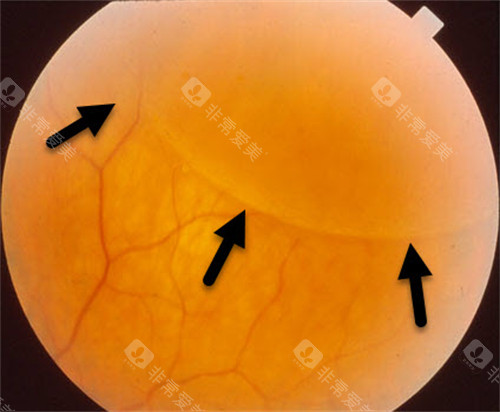

糖尿病视网膜病变,也被称为糖尿病性视网膜病变或糖网病。它是由于糖尿病导致视网膜微血管受损,进而影响视力。

随着病情的发展,患者可能出现视力下降、视物模糊、眼前黑影等症状,重度时甚至会导致失明,给患者的生活和工作带来极大不便。